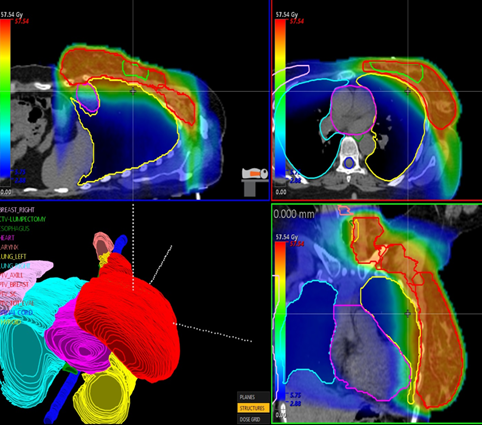

Target: PTV_TOT_EVAL

Dose prescription: 50.0 Gy in 25 fr.

Protocol followed: RTOG-1304 ( Criteria squeezed more ! )

Techniques: 3D-CRT, IMRT, VMAT

Dose calculation grid should be less than 3 mm

PB dose calculation is not allowed to be used

Generated plan should be deliverable (no couch/patient collision)